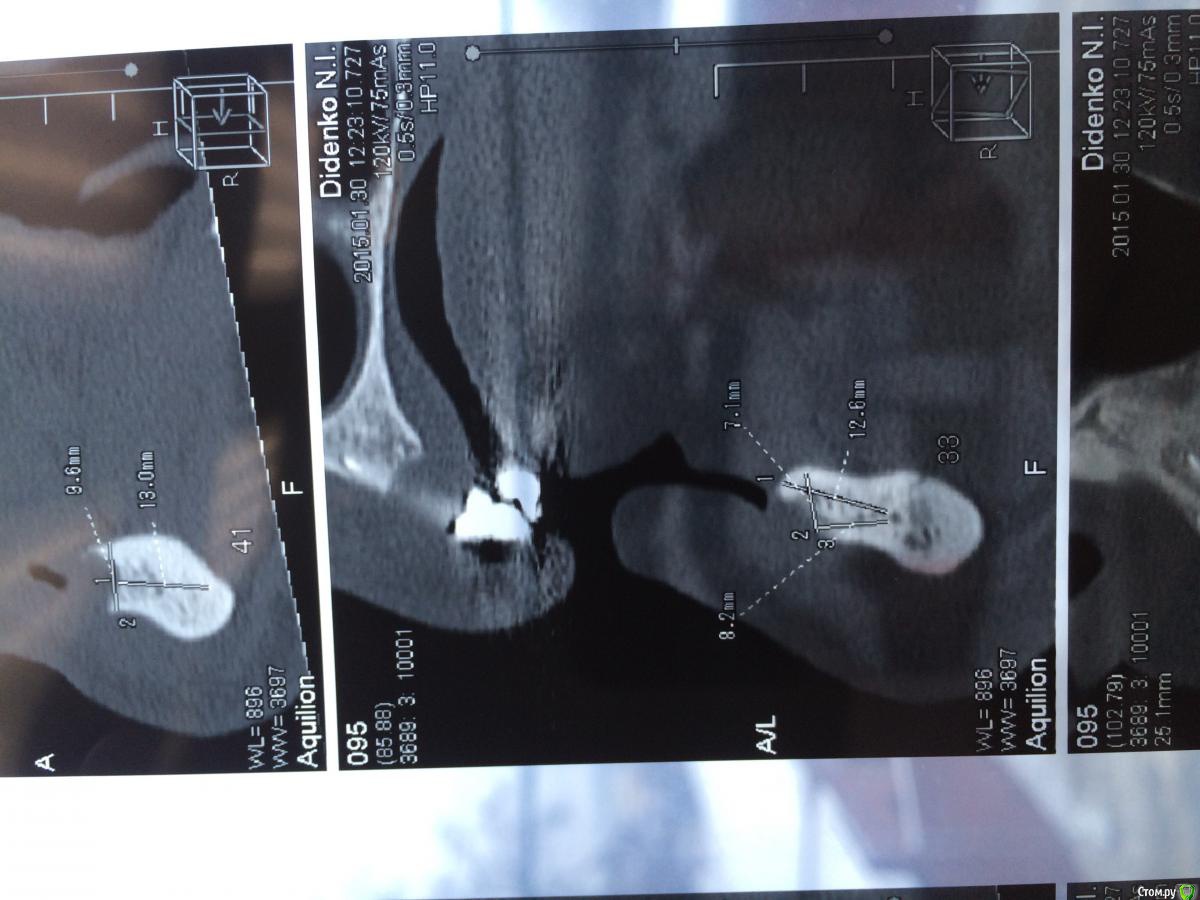

urseva19.05.10 Опубликовано 31 января, 2015 Поделиться Опубликовано 31 января, 2015 Коллеги, в каких позициях на ваш взгляд целесообразнее поставить имплантаты желательно без НКР ( пациент ограничен во времени) что бы в последствии протезироваться съемным протезом на локаторах? На верх не смотрите там все ясно Спасибо! Ссылка на комментарий

Alejandro Опубликовано 31 января, 2015 Поделиться Опубликовано 31 января, 2015 Я бы поставил два межментально в области клыков, и два в области шестёрок тогда. Можно не сильно параллелить - на локаторах это прощается. Ссылка на комментарий

kriokov Опубликовано 31 января, 2015 Поделиться Опубликовано 31 января, 2015 1. выравнивайте гребень2. Позиции 34 , 32, 42, 44, если болты позволяют их субкрестально поставить , то притопите, и ушиться бы двурядно, Ссылка на комментарий

urseva19.05.10 Опубликовано 1 февраля, 2015 Автор Поделиться Опубликовано 1 февраля, 2015 1. выравнивайте гребень2. Позиции 34 , 32, 42, 44, если болты позволяют их субкрестально поставить , то притопите, и ушиться бы двурядно, 1. Всё-таки считаете без НКР не обойтись?2. С 32,42 понятно, а если в области 36,46 установить не будет ли лучше фиксация протеза, да и условия вроде позволяют. Как думаете? Ссылка на комментарий

kriokov Опубликовано 1 февраля, 2015 Поделиться Опубликовано 1 февраля, 2015 1. Всё-таки считаете без НКР не обойтись?2. С 32,42 понятно, а если в области 36,46 установить не будет ли лучше фиксация протеза, да и условия вроде позволяют. Как думаете?1. не знаю, лучше бы просто ОПТГ глянуть и четко срезы в межментальном отделе2. Я не делал так , ставил всегда по просьбе ортопеда в межментальном Ссылка на комментарий